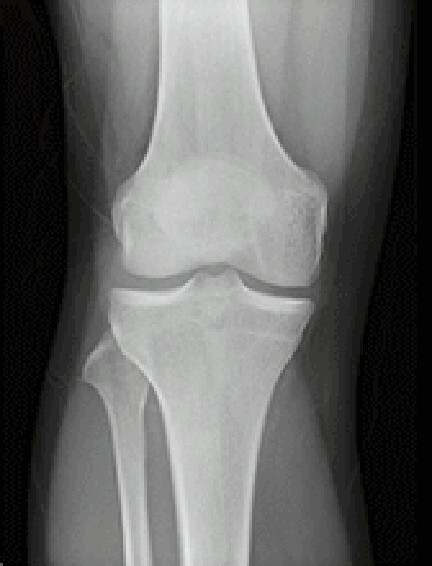

マルチスライスCTスキャナは寝台に横になるだけで頭部・胸部・腹部など体内を断層(輪切り)で撮影できる検査です。

診断や治療のために骨や血管の3D(立体的な三次元画像)を作成することもできます。